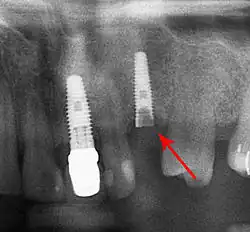

Od těchto teoretických rizik odvozujte komplikace v reálném světě. Dlouhodobá selhání jsou způsobena buď ztrátou kosti kolem zubu a/nebo dásně v důsledku periimplantitidy, nebo mechanickým selháním implantátu. Protože na implantátu není zubní sklovina, nedochází k jeho selhání v důsledku zubních kazů jako u přirozených zubů. Přestože rozsáhlých dlouhodobých studií není mnoho, několik systematických přehledů odhaduje dlouhodobou (pětiletou až desetiletou) životnost zubních implantátů na 93–98 % v závislosti na jejich klinickém použití.[1][2][3] Během počátečního vývoje zubních implantátů byly všechny korunky připevněny k zubům pomocí šroubů, ale novější pokroky umožnily umístění korunek na opěrky pomocí dentálního cementu (podobně jako při nasazování korunky na zub). Tím vznikla možnost, že cement, který unikne zpod korunky při cementaci, se zachytí v dásni a vytvoří periimplantitidu (viz obrázek níže). Ačkoli se tato komplikace může vyskytnout, nezdá se, že by u cementovaných korunek docházelo k dalším periimplantitidám ve srovnání se šroubovanými korunkami celkově.[59] U složených implantátů (dvoustupňových implantátů) jsou mezi vlastním implantátem a nadstavbou (abutmentem) mezery a dutiny, do kterých mohou pronikat bakterie z dutiny ústní. Později se tyto bakterie vrátí do přilehlých tkání a mohou způsobit periimplantitidu.